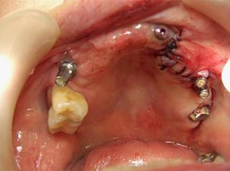

本来ならば治療順が逆ですが臼歯部確立後、右側2・3、左側3・4破折・腫脹を呈してきたため抜歯ならびに左上前歯部には垂直的にオンレーグラフトをおこないます。

右側5インプラント体の頬側面の骨欠損にもCAPおよびバイオス使用予定です。 |

| 左上4番インプラント体頬側面にCAPとオンレーグラフト、さらにバイオスを使用しています。 |